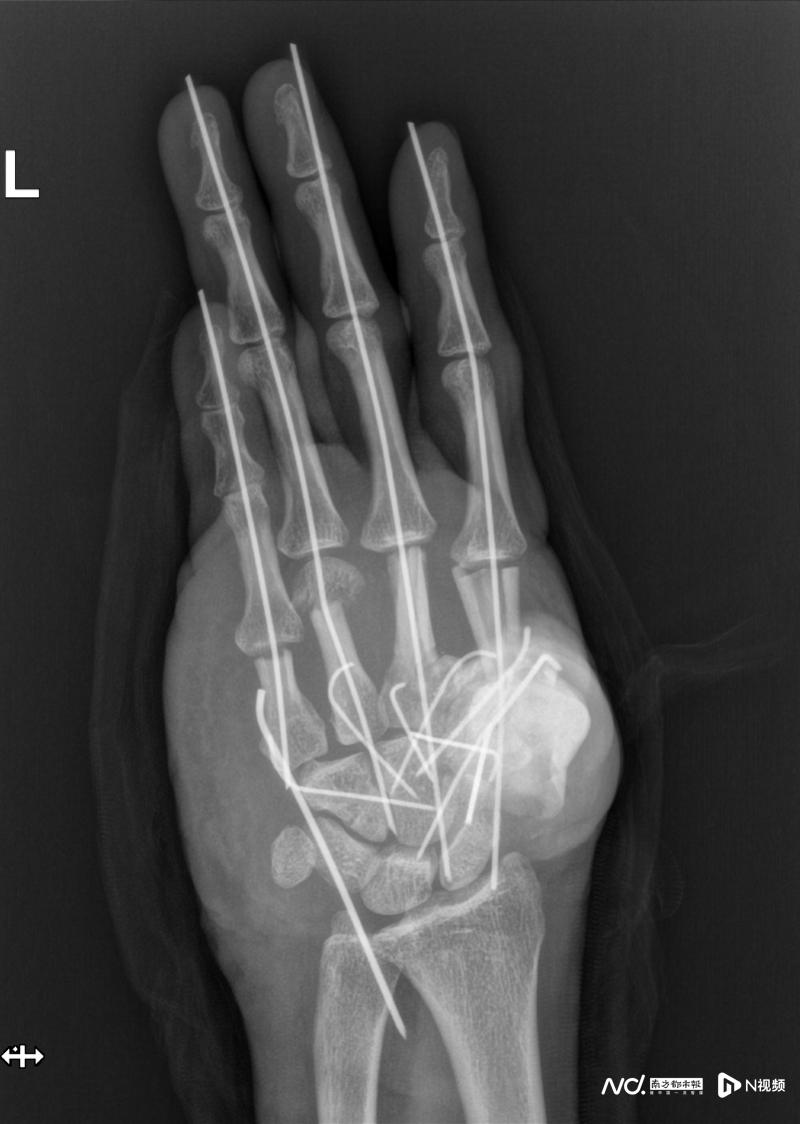

時間就是生機(jī)!王小立團(tuán)隊迅速啟動急診綠色通道,1小時內(nèi)完成術(shù)前準(zhǔn)備并制定詳細(xì)方案。無影燈下,手術(shù)分秒必爭:團(tuán)隊首先徹底清創(chuàng),清除拇指毀損部分及粉碎骨塊,隨后對掌骨、腕掌關(guān)節(jié)進(jìn)行精準(zhǔn)復(fù)位,用克氏針固定骨折端。

真正的挑戰(zhàn)在于重建左手血運(yùn)。由于手掌、手背的主干血管嚴(yán)重?fù)p毀,醫(yī)生決定從患者右足內(nèi)側(cè)截取大隱靜脈,將其裁剪成多段“血管橋”,像繡花般精細(xì)吻合至左手掌背側(cè)。“每條血管直徑不足2毫米,需在顯微鏡下一針一線縫合,稍有不慎就會導(dǎo)致失敗。”何天頌解釋,團(tuán)隊最終完成11條血管(共22個吻合口)的橋接,成功恢復(fù)各指體血供。

手術(shù)團(tuán)隊連續(xù)奮戰(zhàn)11小時,成功挽救了傷者的手掌。

另一難題是創(chuàng)面覆蓋。手掌、手背撕脫的皮膚因挫傷嚴(yán)重已無存活可能,若強(qiáng)行縫合將引發(fā)感染。王小立當(dāng)機(jī)立斷,從患者大腿前外側(cè)切取一塊帶血管的游離皮瓣,移植至左手創(chuàng)面,并與腕部血管精密對接。“這相當(dāng)于在手上‘種’了一塊新皮膚。”何天頌說。11小時的奮戰(zhàn)中,醫(yī)生還修復(fù)了8條神經(jīng)和18條肌腱,近乎重建了一只手的“動力系統(tǒng)”。